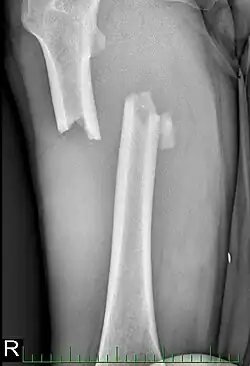

Fixadores externos (tutores) podem ser usados para evitar mais danos para a perna até que o paciente esteja estável o suficiente para a cirurgia. É normalmente usado apenas como uma medida temporária para manter o osso e articulações mais alinhados e estáveis. No entanto, para alguns casos mais complicados pode ser usado como uma alternativa para haste intramedular em um tratamento de largo prazo.[11][12]

Para fraturas da diáfise, a redução e haste intramedular são recomendados atualmente. O osso é realinhado, e em seguida uma haste de metal é fixada atravessando a medula óssea. A haste é estabilizada com pregos em cada extremidade. Este método oferece menos exposição, 98% de consolidação, menores taxas de infecção (1%-2%) e menos cicatrizes.[13]